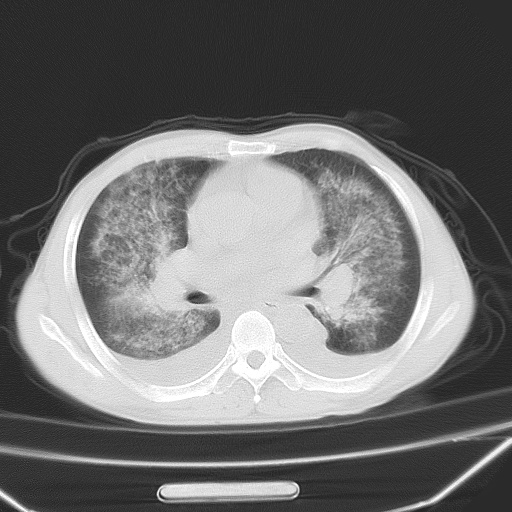

男、42岁、咯血3天。既往有甲亢、贫血、血尿蛋白尿史多年。血象:wbc:6.   中性粒:70.6%。

双肺野对称性磨玻璃影,分布于内中带,双侧胸水,患者有咯血。

双肺野广泛对称性磨玻璃影、实变影,以肺门为中心,主要分布于内中带,符合典型肺泡性肺水肿;伴双侧胸腔少量游离积液。结合患者既往病史且咯血就诊,支持多因素(尿毒症等)所致之肺水肿、肺出血、胸水;影像表现暂不考虑心源性水肿,且症状也不太符。需密切随诊结合临床治疗等进一步明确。

心影增大密度略低,双肺磨玻璃样高密度影及双侧胸腔积液,考虑心功能不全继发双肺肺水肿及双侧胸腔积液。心影密度略低,考虑贫血所致。